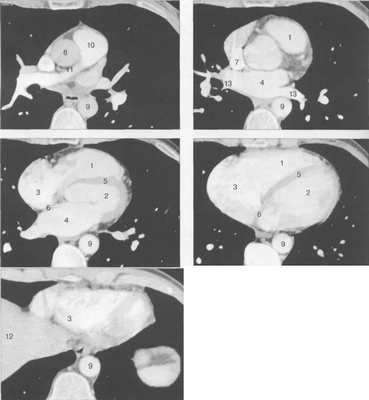

КТ АНАТОМИЯ СЕРДЦА

КТ-исследование позволяет получать поперечные (аксиальные) сечения сердца. Стандартная пошаговая КТ и даже спиральная КТ не получили распространения для исследования морфологии и функции сердца. Более тщательный анализ внутрисердечных структур возможен с помощью многослойной спиральной КТ (МСКТ) в условиях внутривенного контрастирования. КТ-изображения сердца и сосудов на различных уровнях представлены на рис. 9.34.

Рис. 9.34. КТ сердца и сосудов.

1 — правый желудочек; 2 — левый желудочек; 3 — правое предсердие; 4 — левое предсердие; 5 — межжелудочковая перегородка; 6 — межпредсердная перегородка; 7 — верхняя полая вена; 8 — восходящая часть аорты; 9 — нисходящая часть аорты; 10 — легочный ствол; 11 — правая легочная артерия; 12 — диафрагма; 13 — легочные вены.

МСКТ в условиях внутривенного болюсного контрастирования позволяет визуализировать коронарные артерии (МСКТ-коронарография). Анализ состояния коронарных артерий выполняется сначала на аксиальных срезах (рис. 9.35). В постпроцессинговой обработке изображений используются различные виды реконструкций: многоплоскостные реформации (MPR), проекция максимальной интенсивности (MIP), трехмерные (VRT) (рис. 9.36).